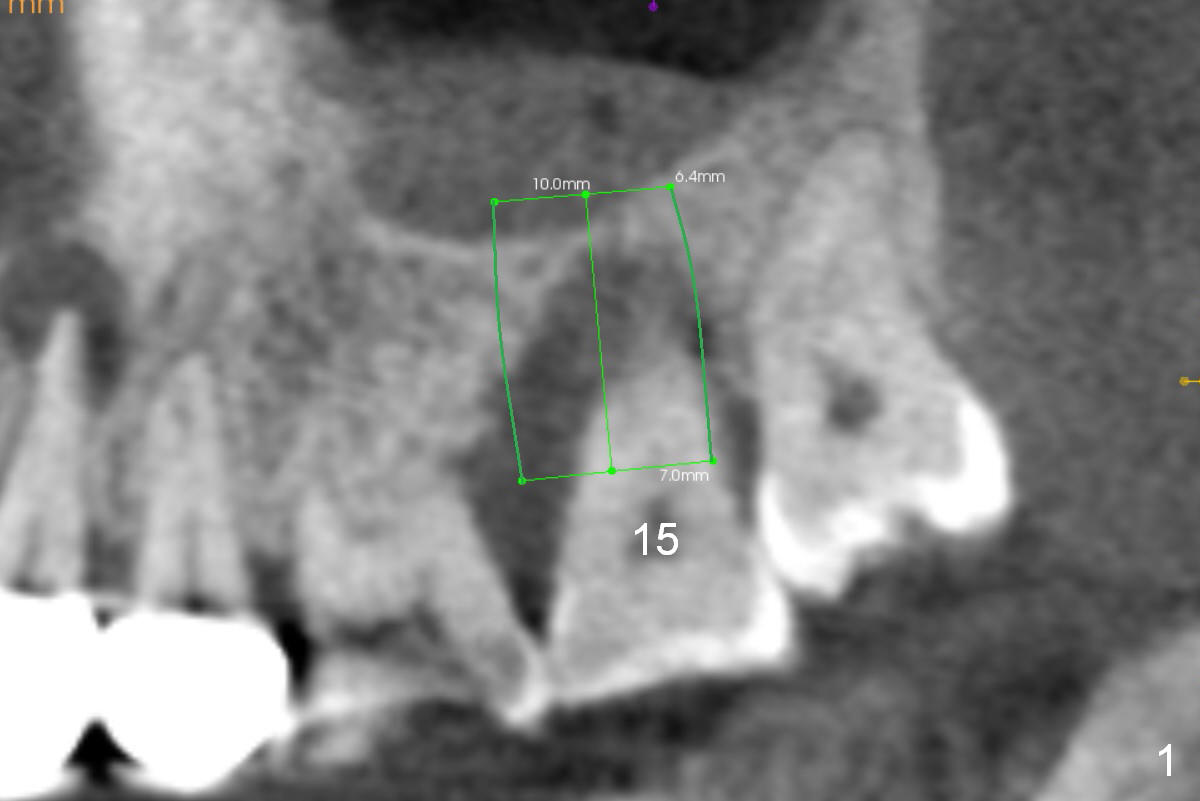

A 42-year-old lady (HJ) has advanced periodontitis at #15 (Fig.1 (CBCT sagittal section)). The buccal (B) plate is thin (Fig. 2 (coronal section), 3 (axial section)). The apical bone is also thin (Fig.1,2). A 7x10 mm implant is placed in a position so that the implant contacts the mesial, palatal and distal walls of the socket (treated with 2% Xylocaine with 1:50,000 Epinephrine) for primary stability (Fig.3). The buccal gap will be filled with Osteogen Plug apically (Fig.4 purple rectangles) and bone graft coronally (red circles). SM implant (Fig.4) is more tapered than UF one (Fig.2), easier to insert.